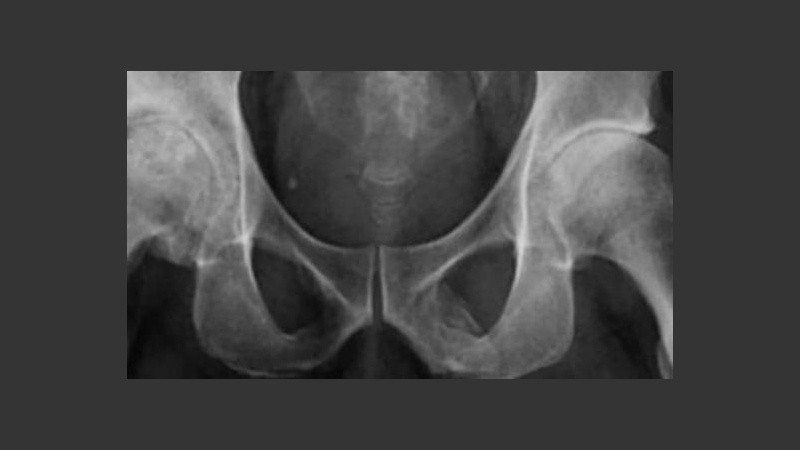

En las imágenes se mostraba una extensa calcificación de los tejidos blandos que forman el pene. Esto ocurre cuando se depositan sales de calcio en los tejidos blandos del órgano, provocando la aparición de placas de hueso donde no debería de haberlas. El caso es muy curioso y hay sólo 40 registros a nivel mundial según un informe médico publicado en la revista Urology Case Reports.